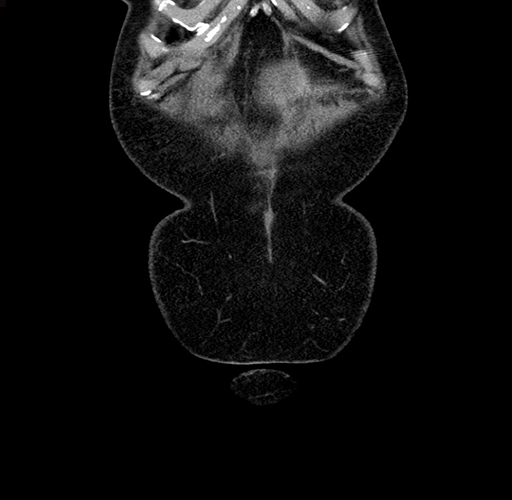

MRI T1